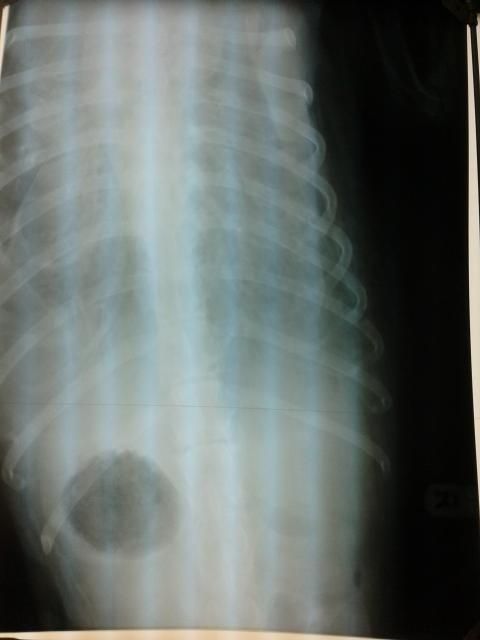

Bij de da aangekomen was het voor haar duidelijk, compliment dat ik het had opgemerkt. Er moest een foto gemaakt worden, dat ging dramatisch. Bluf lag op haar zij en raakte in paniek, met als gevolg een volledige paarse tong. Ik schrok me rot en da overigens ook, zo weinig lucht had ze blijkbaar nog maar. Buikfoto gemaakt ipv op de zij.

Ik heb foto's van de foto gemaakt. Ze heeft veel verteld en uitgelegd, maar ik ving maar een deel op. Allemaal vocht, en heel weinig lucht.

De witte puntjes duiden op de longontsteking die ze eroverheen heeft gekregen, want de constatering is dat haar hart het aan het begeven is. Een goede hartfoto kon echter niet gemaakt worden.